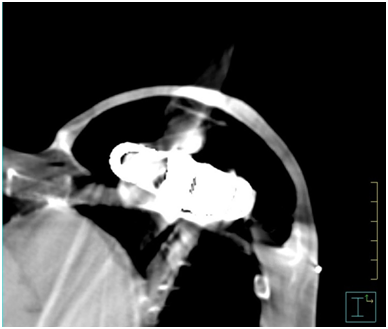

Figure 1 shows an example of an air expander in situ on a CT transverse slice. Between March 2016 and August 2018, data was collected prospectively from eight female patients fitted with the AeroForm™ implant who were referred to our institution for post-operative radiotherapy. The objective was to develop a treatment planning protocol using the Pinnacle3 Treatment Planning System (TPS) v9.10 (Philips, USA). All patients underwent a computed tomography (CT) scan as per our standard breast treatment simulation protocol on the Optima CT 580 RT (GE Healthcare) scanner. All treatment plans were generated for the Elekta Synergy linear accelerator with AgilityTM head (Elekta, Sweden), and collapsed cone algorithm beam modelling was carried out in the TPS. The slice thickness of all CT scans was 2.5 millimetres (mm), and these were calculated on a 3mm dose grid size in the TPS. The radiation oncologist defined the treatment area by marking the superior level, inferior level, medial border and posterior border on the patient. These borders defined the beam shape of the multi-leaf collimator (MLC) using the beams eye view in the TPS.

Figure 1 AeroForm™ implant on a transverse slice CT scan. Main components visible are the centrally placed CO2 canister encompassed by a permeable silicone casing.